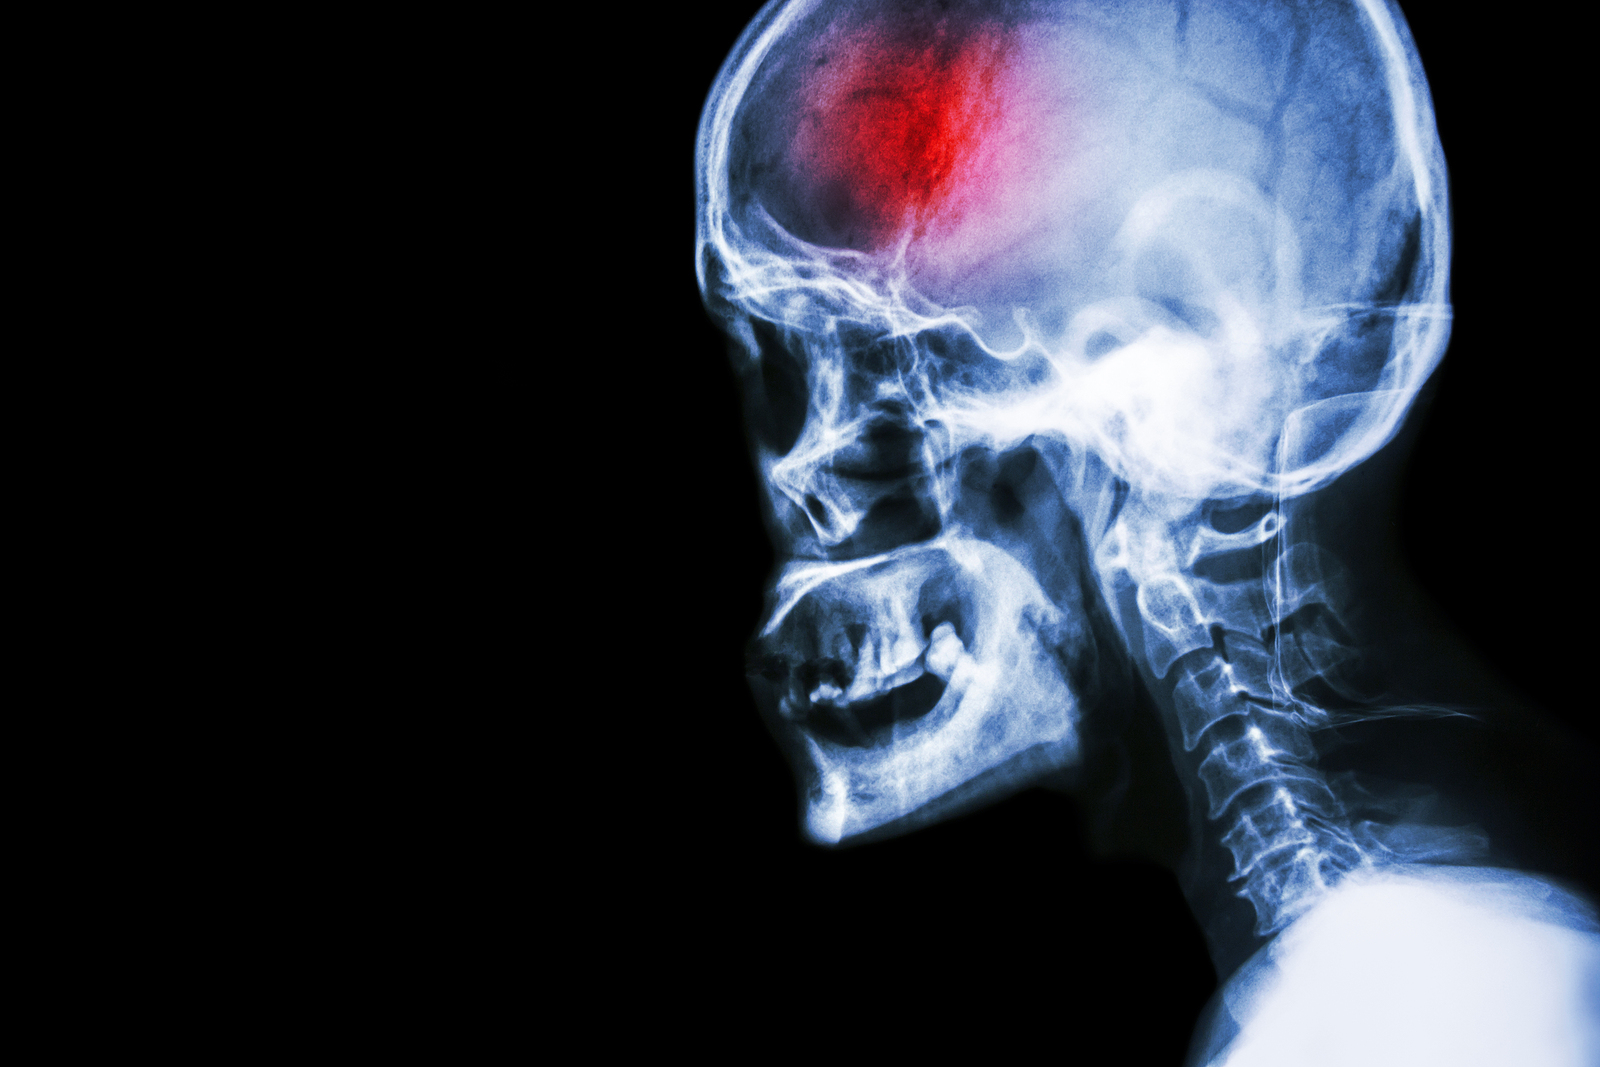

A stroke (previously known as a cerebrovascular accident) when there is a decreased flow of blood to the brain from either a blockage in the blood vessels that supply the brain (ischemic stroke), or a bleed from the blood vessels that supply the brain (hemorrhagic stroke). When the blood flow to the brain is blocked it prevents the brain from getting the needed oxygen and nutrients to function. Without oxygen the brain cells can be permanently damaged or die and the physical and mental functions related to that area of the brain will be affected. A stroke is a medical emergency and rapid treatment is crucial to decreasing the damage caused by a stroke.

• Ischemic stroke: a stroke that is caused by a blockage (clot) that disturbs the blood flow to the brain.

• Hemorrhagic stroke: a stroke that is caused by a bleed that disturbs the blood flow to the brain and puts pressure on the surrounding tissue.

A bleed in the brain can occur due to several reasons. Aneurysms are balloon-like bulges in the brain that can burst causing a bleed. Aneurysms can be a malformation you are born with or can occur due to atherosclerosis.

Computed Tomography (CT) scan and/or Magnetic Resonance Imaging (MRI) scan: These tests are done on your brain and used to locate the exact location of the stroke and to determine if it has been caused by a blockage or a bleed. These tests can also help rule out other conditions that may be causing symptoms, such as an infection or a brain tumour